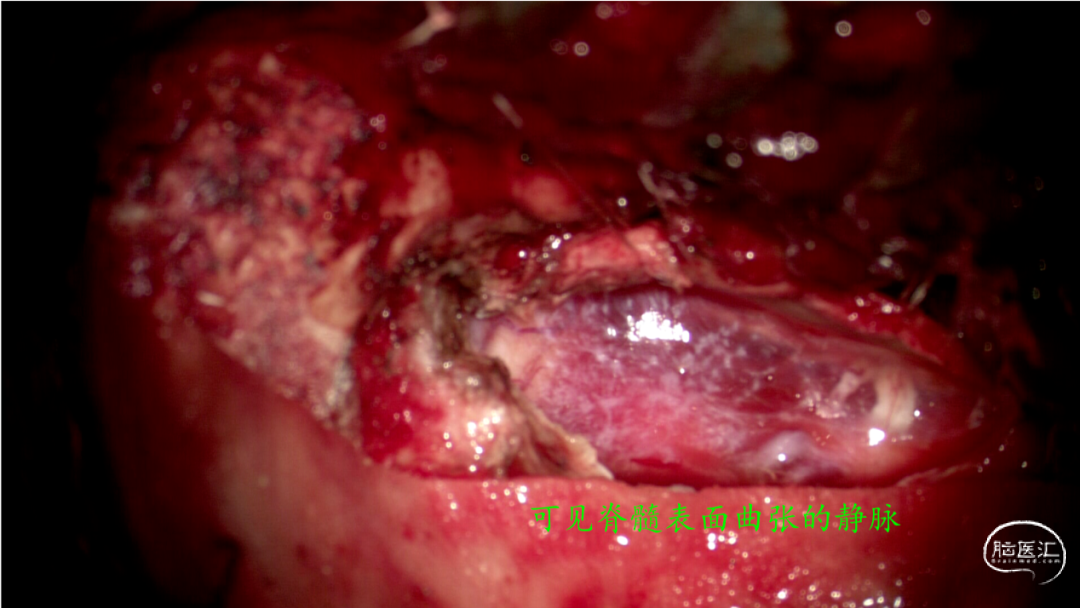

手术过程:

视频